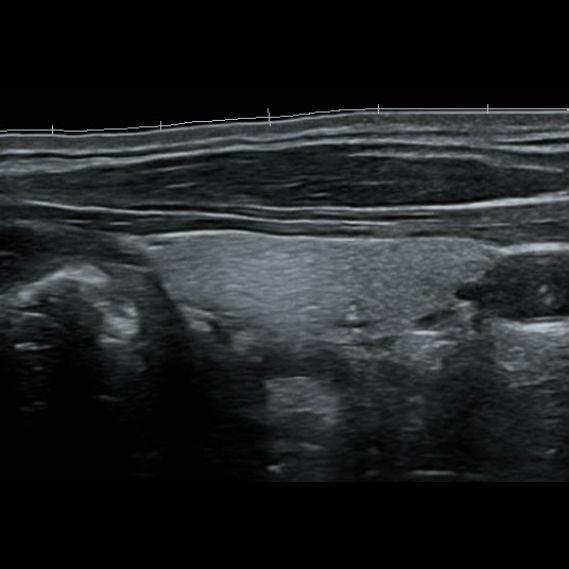

Нажав кнопку iScape мы просто проводим датчик вдоль оси сканирования, и прибор сопоставляет сканируемые изображения в единую, практически бесконечно длинную картину. Теперь влезет всё и продольное сечение щитовидной железы, и широкие гематомы, и крупные кисты Бейкера, и ахиллово сухожилие во всю длину с подробным указанием точек надрыва и указанием расстояния от пяточной кости для уточнения топики травмы даже при изгибе контактной поверхности.